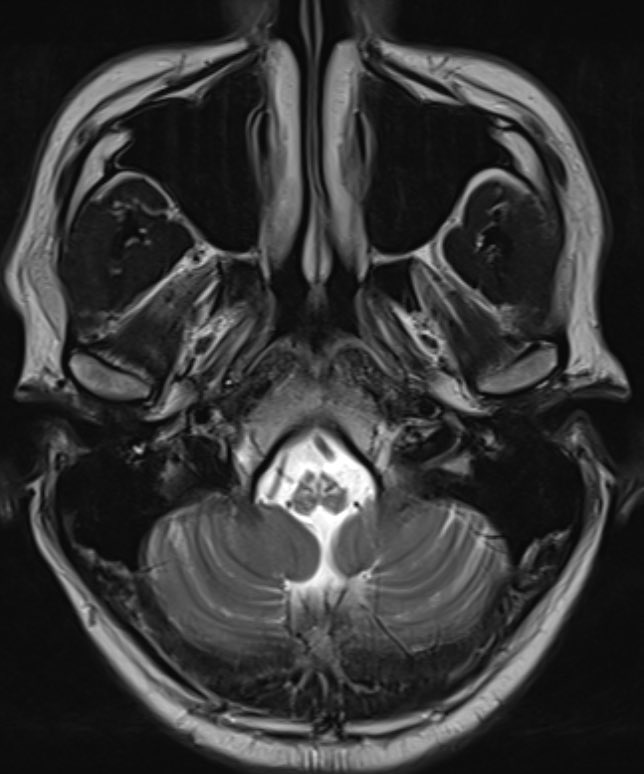

@nodisability I think it is the symmetry on MRI + location+ presentation + family history

@bobvarkey What's classical to think GFAP mutation in MRI here? Owls eye?

Clinical exome sequencing shows GFAP mutation consistent with

🧠 Alexander Disease

Final Dx - Alexander Disease Bulbospinal variant

🔬 Pathophysiology

• Cause: Gain-of-function mutations in GFAP gene (chromosome 17q21)

• Hallmark: Rosenthal fibers — protein aggregates in astrocytes containing GFAP, heat shock proteins, ubiquitin

• Mechanism: Abnormal GFAP crosslinking via oxidation and ubiquitination (Lin et al., 2024)

👤 Clinical Phenotypes

Revised Classification (2011):

• Type I: Cerebral, early onset, median survival ~14 years

• Type II: Bulbospinal, later onset, median survival ~25 years

🩺 Diagnosis

• MRI: 4 of 5 criteria needed (frontal WM predominance, periventricular rim, basal ganglia abnormalities, brainstem involvement, contrast enhancement)

• Genetic testing: Confirms diagnosis